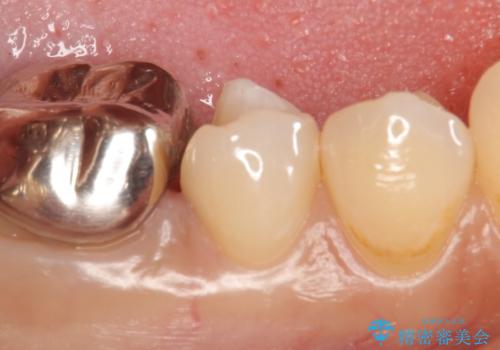

- 右下5番目の歯がしみるといらっしゃった方の症例です。

銀歯及び虫歯を除去し、適合に優れたPGA(ゴールド)インレーにて修復を行いました。

ゴールドは化学的な安定性が高いため変色や腐食がほとんどなく、アレルギーなども起こりにくい人体に優しい素材です。

また硬さも天然歯に近いため周囲の歯への影響も少なく、さらに適合もよいため虫歯の再発も少ない、とても補綴に適した材料です。